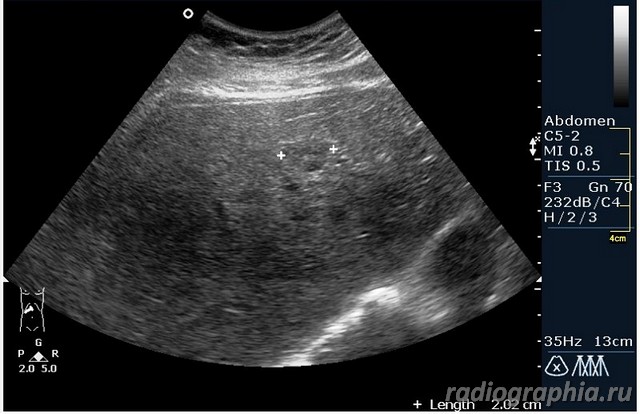

УЗИ печени. Женщина 37 лет. Жалобы на боли в эпигастрии; в печени обнаружено такое образование...

Считаю,что это опухоль,имеет неоднородную структуру,четкий контур,прорастает в сосуд(есть один такой скан) И,вообще,вся поверхность печени НЕСПОКОЙНАЯ,могут быть мелкие МТ.Интересно,что на КТ?

так и хочется назвать это метастазами но уж очень они красивые и доброжелательние по структуре (изоехогенные по отношению к структуре печени) и они больше компресирують чем проростают, склонен к ответу о доброкачественной гиперплазии. так что же на КТ?

Спсибо,но...вся печень какая-то неоднородная.